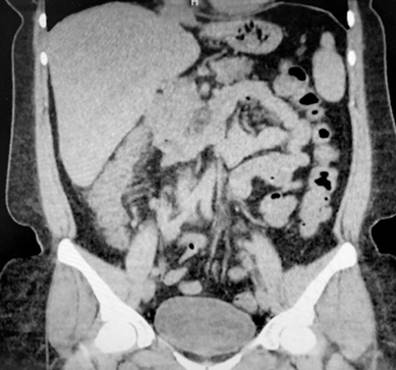

Se trata de una paciente femenina de 43 años con antecedente de EA desde los 20 años (tratamiento previo con etanercept, adalimumab, abatacept y desde 2017 secukinumab), fibromialgia, hipertensión arterial, hipotiroidismo y tuberculosis latente tratada en 2019, quien consultó por clínica de una semana de evolución caracterizada por dolor abdominal difuso asociado a deposiciones diarreicas sanguinolentas múltiples (más de 15 al día). Al ingreso estaba taquicárdica, deshidratada, afebril y con dolor de predominio en el hemiabdomen inferior sin signos de irritación peritoneal. Se realizaron laboratorios en los que el hemograma resultó sin alteración de las líneas celulares, y el estudio ecográfico y tomográfico informaron engrosamiento mural de las paredes del colon derecho con realce mucoso, adenopatías mesentéricas múltiples y escaso líquido libre en el fondo del saco (Figura 1). Se realizó una colonoscopia en la que se encontró edema, eritema, friabilidad de la mucosa, pérdida del patrón vascular y ulceraciones cubiertas por fibrina desde el recto hasta el ciego, hallazgos compatibles con colitis ulcerativa extensa (Figura 2).

Figura 2 Hallazgos endoscópicos. Edema, eritema, pérdida del patrón vascular y ulceraciones cubiertas por fibrina. Fuente: archivo de los autores.